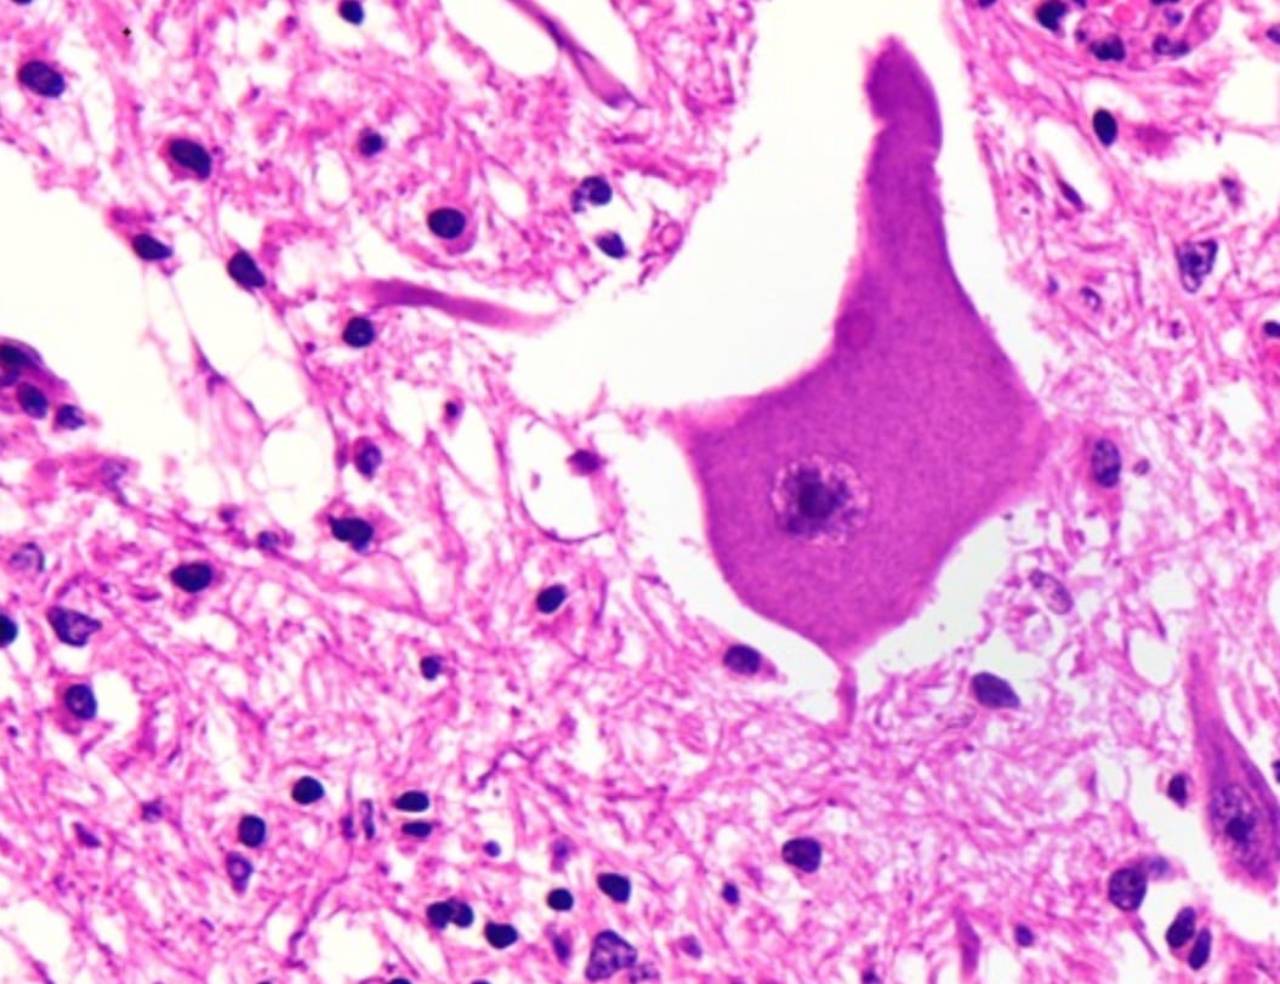

Coleta de amostras para diagnóstico de raiva após a morte.

São colhidas amostras de encéfalo (cérebro) e encaminhada para testes específicos.

Geralmente realizado juntamente com o exame necroscópico, entretanto pode ser feito separadamente pela nossa equipe à campo ou encaminhada cabeça para abertura no laboratório.